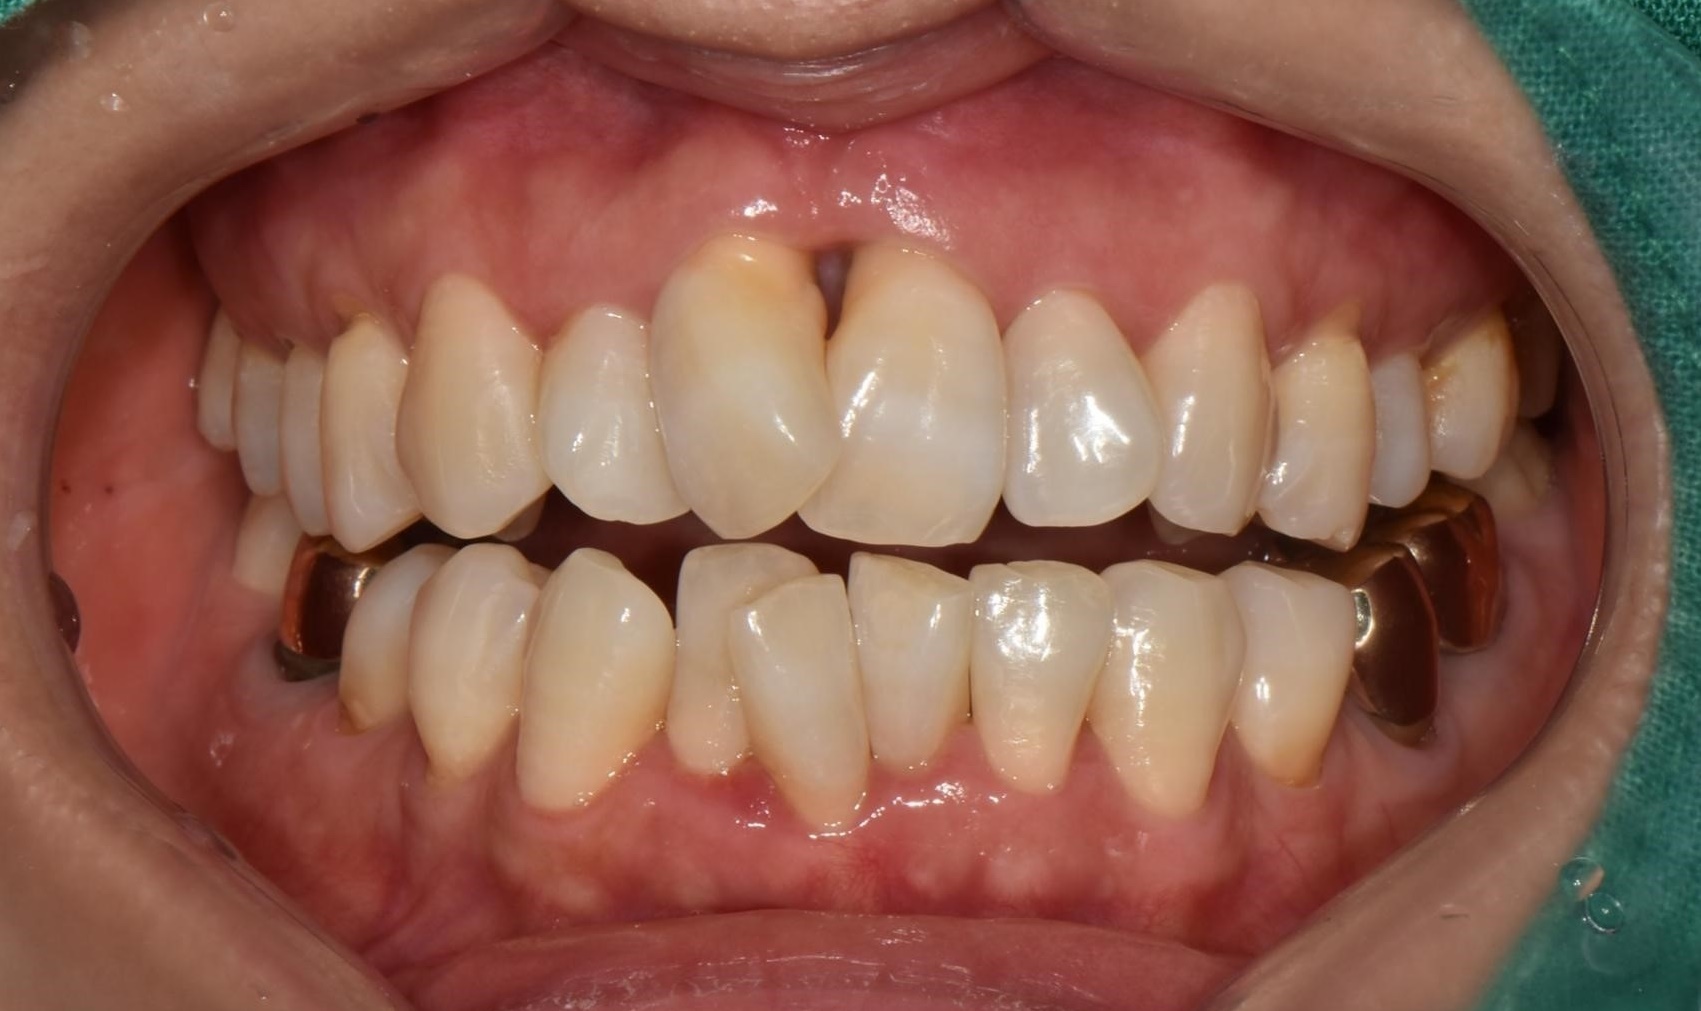

수술 전

수술 후

상하악 구치부 임플란트 식립사례

전후사진